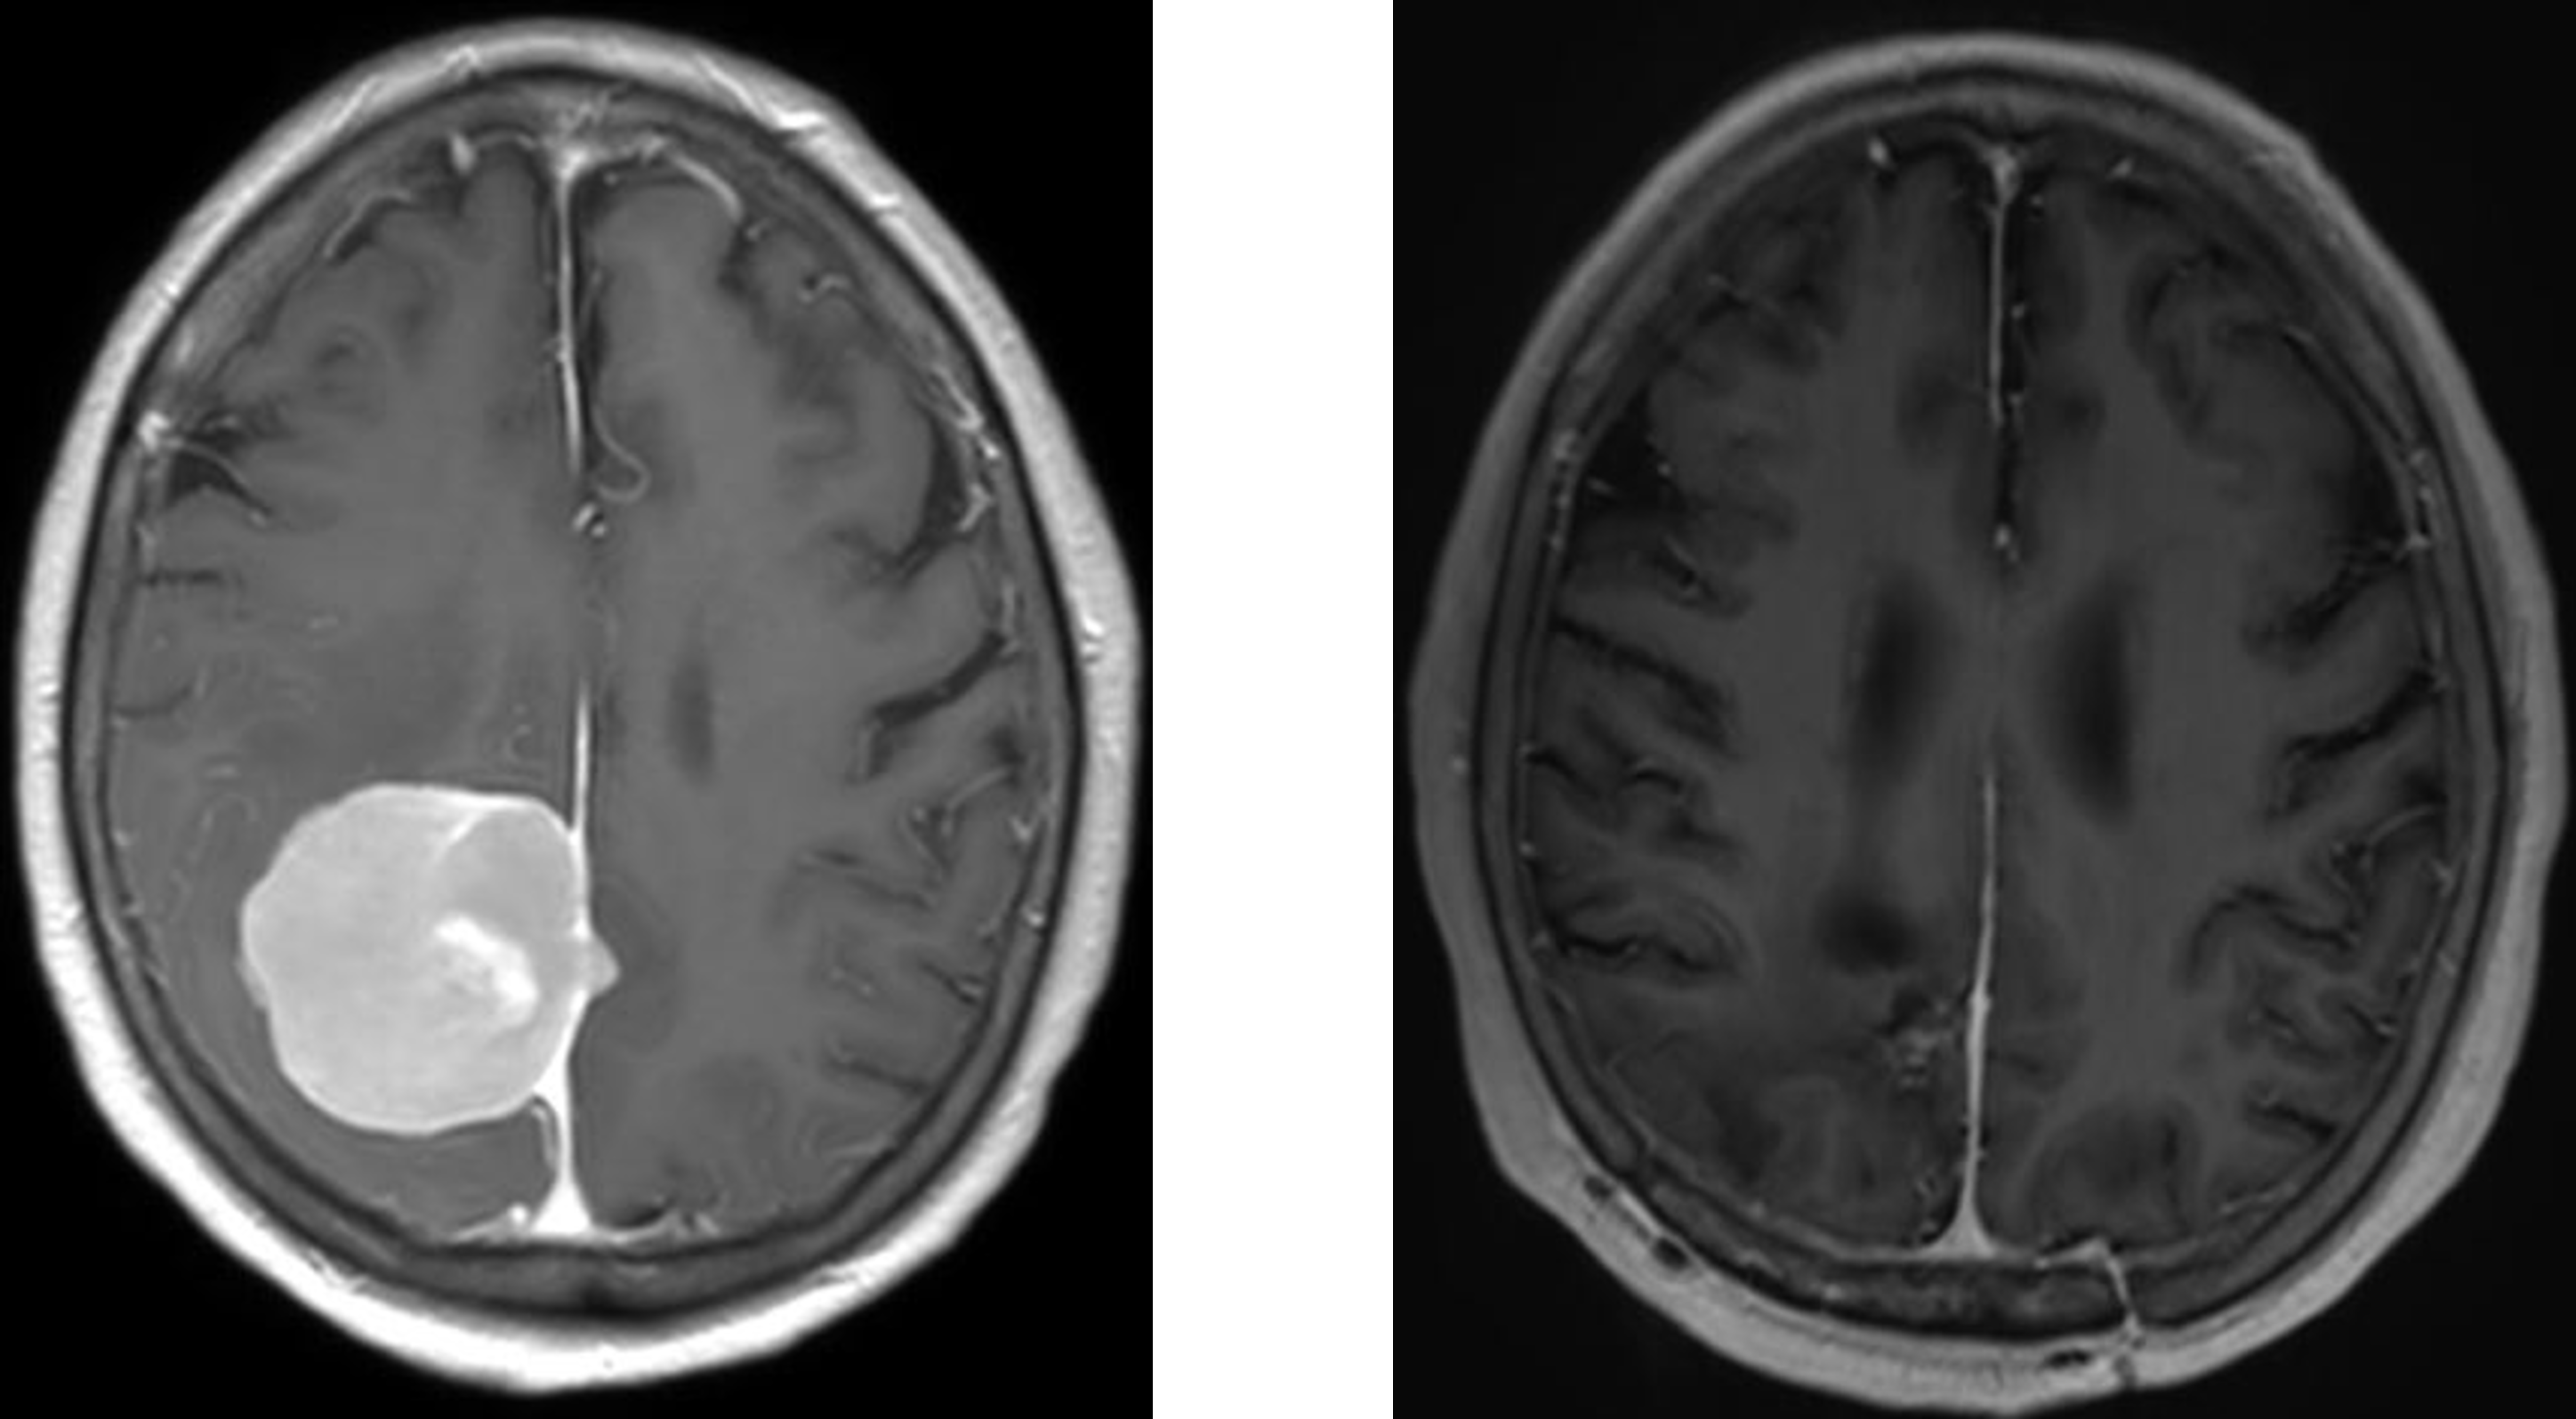

転移性脳腫瘍

転移性脳腫瘍は、頭蓋内以外のがん病巣より、主に血行性転移を起こした疾患です。一般的に、病変や3㎝以上の大きさで、原発巣のコントロールが比較的良く、少なくとも6カ月以上の生存が見込める症例が手術適応となります。手術により局在症状、脳圧亢進症状の改善を図ることにより、日常生活動作を維持したり生活の質(クオリティ・オブ・ライフ)の回復を目指すことで、がん治療を継続できることが目標になります。

それ以外の転移性脳腫瘍は、全脳照射や定位放射線治療(サイバーナイフやガンマナイフ、ライナックナイフなど)といった定位放射線療法が有効な場合があります。転移巣が複数ある場合が多くある場合にも有効な治療法になります。大阪大学やその他、放射線治療可能施設と連携しており、治療を行っております。我々が参加したJCOG0504試験では、複数ある転移巣の場合も、大きいものは腫瘍を摘出し、残りは定位放射線療法する方法は、標準治療である全脳照射と比較して非劣性であったという結果となっております。